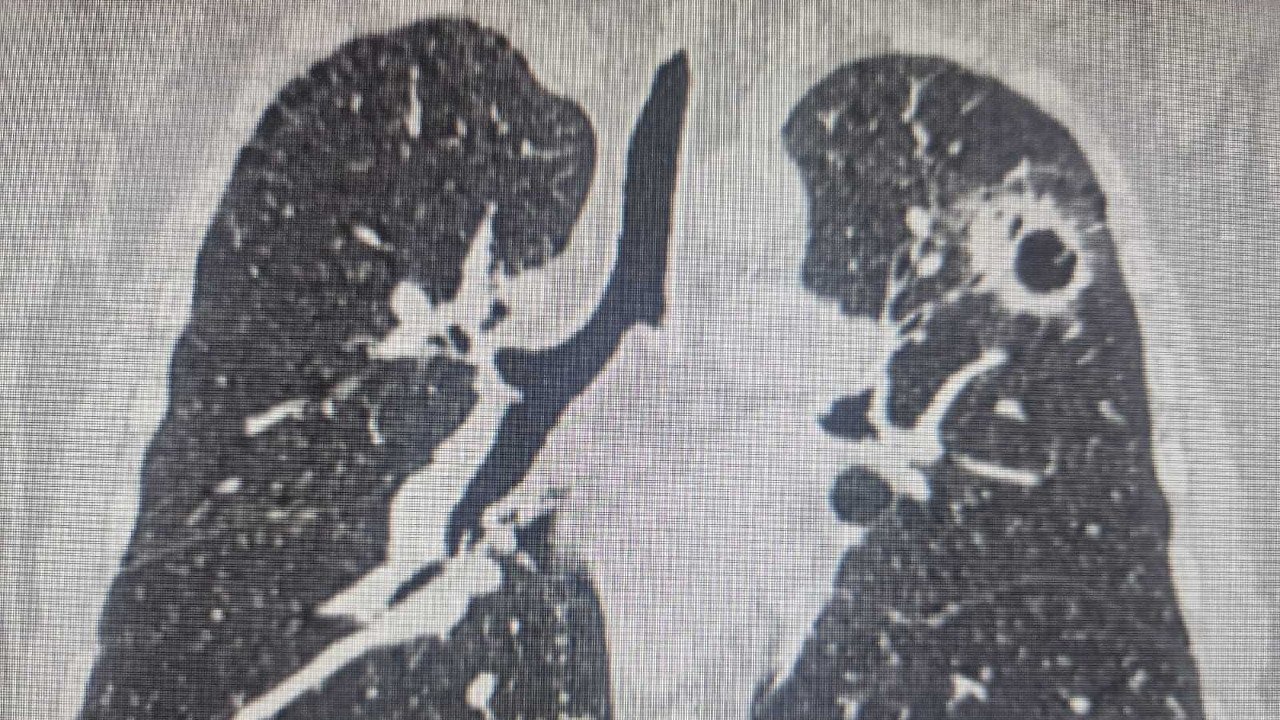

Новосибирцу трижды за 2 года диагностировали рак

Мужчина страдал от злокачественной опухоли лёгких, и врачи практически сотворили чудо.

Три года назад у жителя Новосибирска обнаружили рак правого лёгкого. Врачи решили провести органосохраняющую операцию, удалив часть лёгкого и сохранив его две трети. Через год у пациента выявили рак злокачественную опухоль в левом лёгком.

Вскоре у пациента обнаружилось окологическое заболевание щитовидной железы, и ему пришлось провести вторую операцию. А спустя год рак выявили в левом лёгком. Сейчас пациент проходит химиотерапию. Об этом сообщили в областном Минздраве.

Бронхоангиопластические операции, которые позволяют сохранить лёгкое, становятся все более востребованными благодаря современным методам лечения. По словам врачей, скрининг и отказ от курения могут снизить смертность от рака лёгких. Людям старше 50-лет с большим стажем курения важно регулярно проходить обследования.

По словам заведующего онкологическим отделением №3 (торокальным) Новосибирского онкодиспансера Вадима Козлова, онкология рано или поздно даёт рецидив, но врачи научились продлевать жизнь пациентам благодаря современной лекарственной терапии, таргетной иммунотерапии и новым подходам к хирургическому лечению.